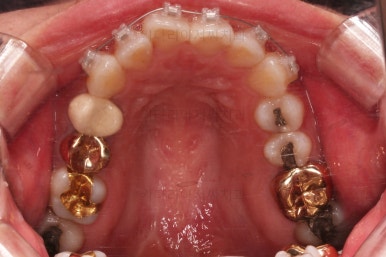

그래서 초기 정렬단계에서는 미니튜브를 이용해 주고, 추후에 좀 더 정교한 조절이 필요한 상황에서는 브라켓장치(엠파워 클리어)로 재부착하기로 했어요.

이번 환자분은 아래 앞니의 높낮이도 맞춰줘야해서 미니스크류까지 이용한 상황이었으나 6개월 정도 걸려서 비교적 발리 마무리 될 수 있었어요.

조금더 디테일을 조절하고 부산부분치아교정 마무리를 합니다.

전후 사진을 비교해 볼게요.

6개월만에 부산부분치아교정 완료했어요.

치열도 가지런해졌고, 웃는 모습도 매우 좋아졌네요.

이상 미니스크류, 미니튜브 등을 이용해 앞니를 부산부분치아교정 했던 치료사례였습니다.